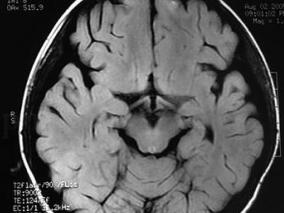

1小时条评论男,50岁,高加索人种,右利手。 主诉:头痛、眩晕5小时。 病史:患者在来急诊室5小时以前正在电脑旁工作,突然出现了后枕部的严重疼痛,随即出现天旋地转感觉,并剧烈地恶心和呕吐,不敢睁眼。没有耳鸣、视物成双和肢体活动的障碍,意识清楚,言语流利。由于休息...